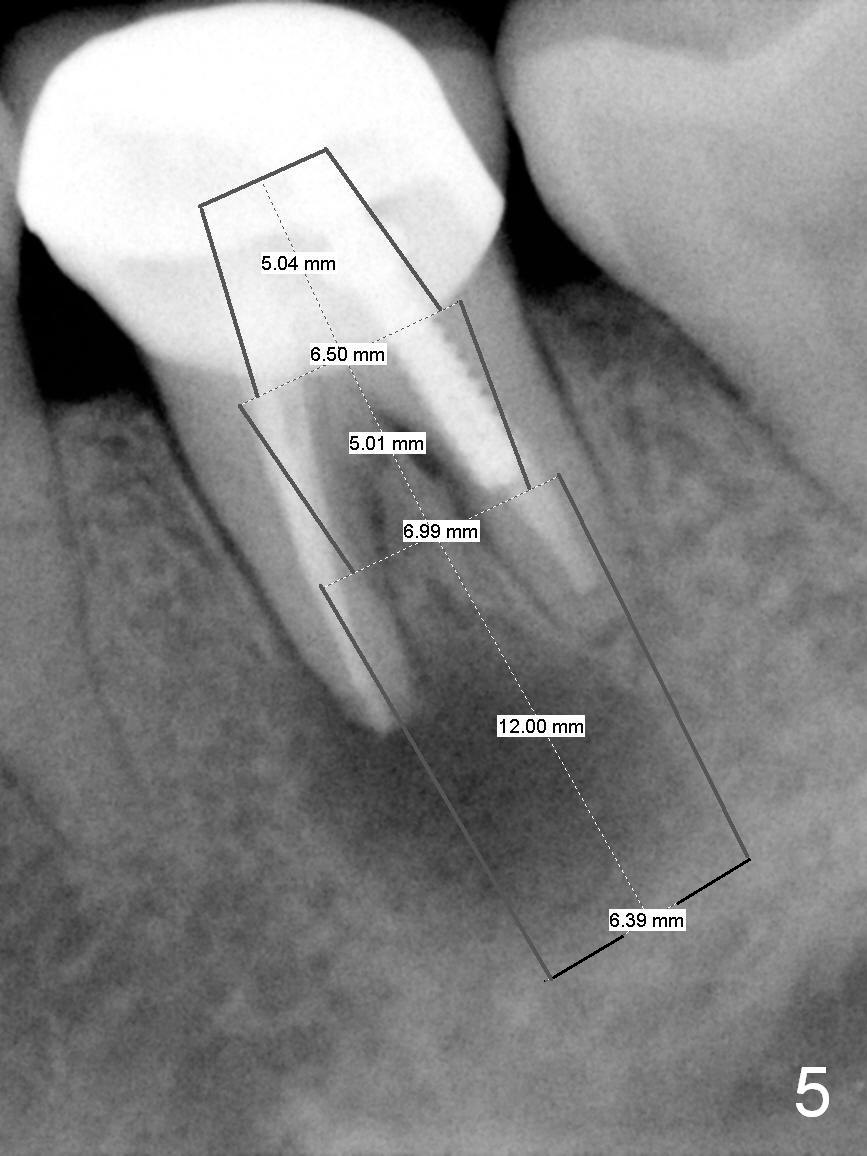

A 58-year-old lady has a long-standing periapical lesion with several episodes of acute infection (Fig.1-3, taken 10, 9 and 2 years ago, respectively). Explore the socket for size and wall integrity (Clindamycin). If the bony defect is not extensive, place a longest implant (18 mm bone-level, 20 mm tissue-level) with moderate diameter (5.5, 6 mm). Otherwise use a shorter, but wider tapered implant (7x12 mm (bone-level), 7 or 8x17 mm (tissue-level)). If the socket is extremely large, consider using 7 or 8 x20 mm cylindrical tissue-level implant. Use Bicon 2 mm pilot drill with extension to measure the socket depth and obtain 3-6 mm new bone or until 20 mm (gingival margin). Take PA. The 1st option is to use UF 3-4.7x18 mm drills at 50 RPM. Make sure that the depth is reached (septum crestal level) and check osteotomy wall integrity after each drill. Then place a 5 or 5.5x16 or 18 mm implant (Fig.6). The 2nd and 3rd options are shown in Fig.4 and 5. Due to severe infection and pain, a shorter implant is placed.